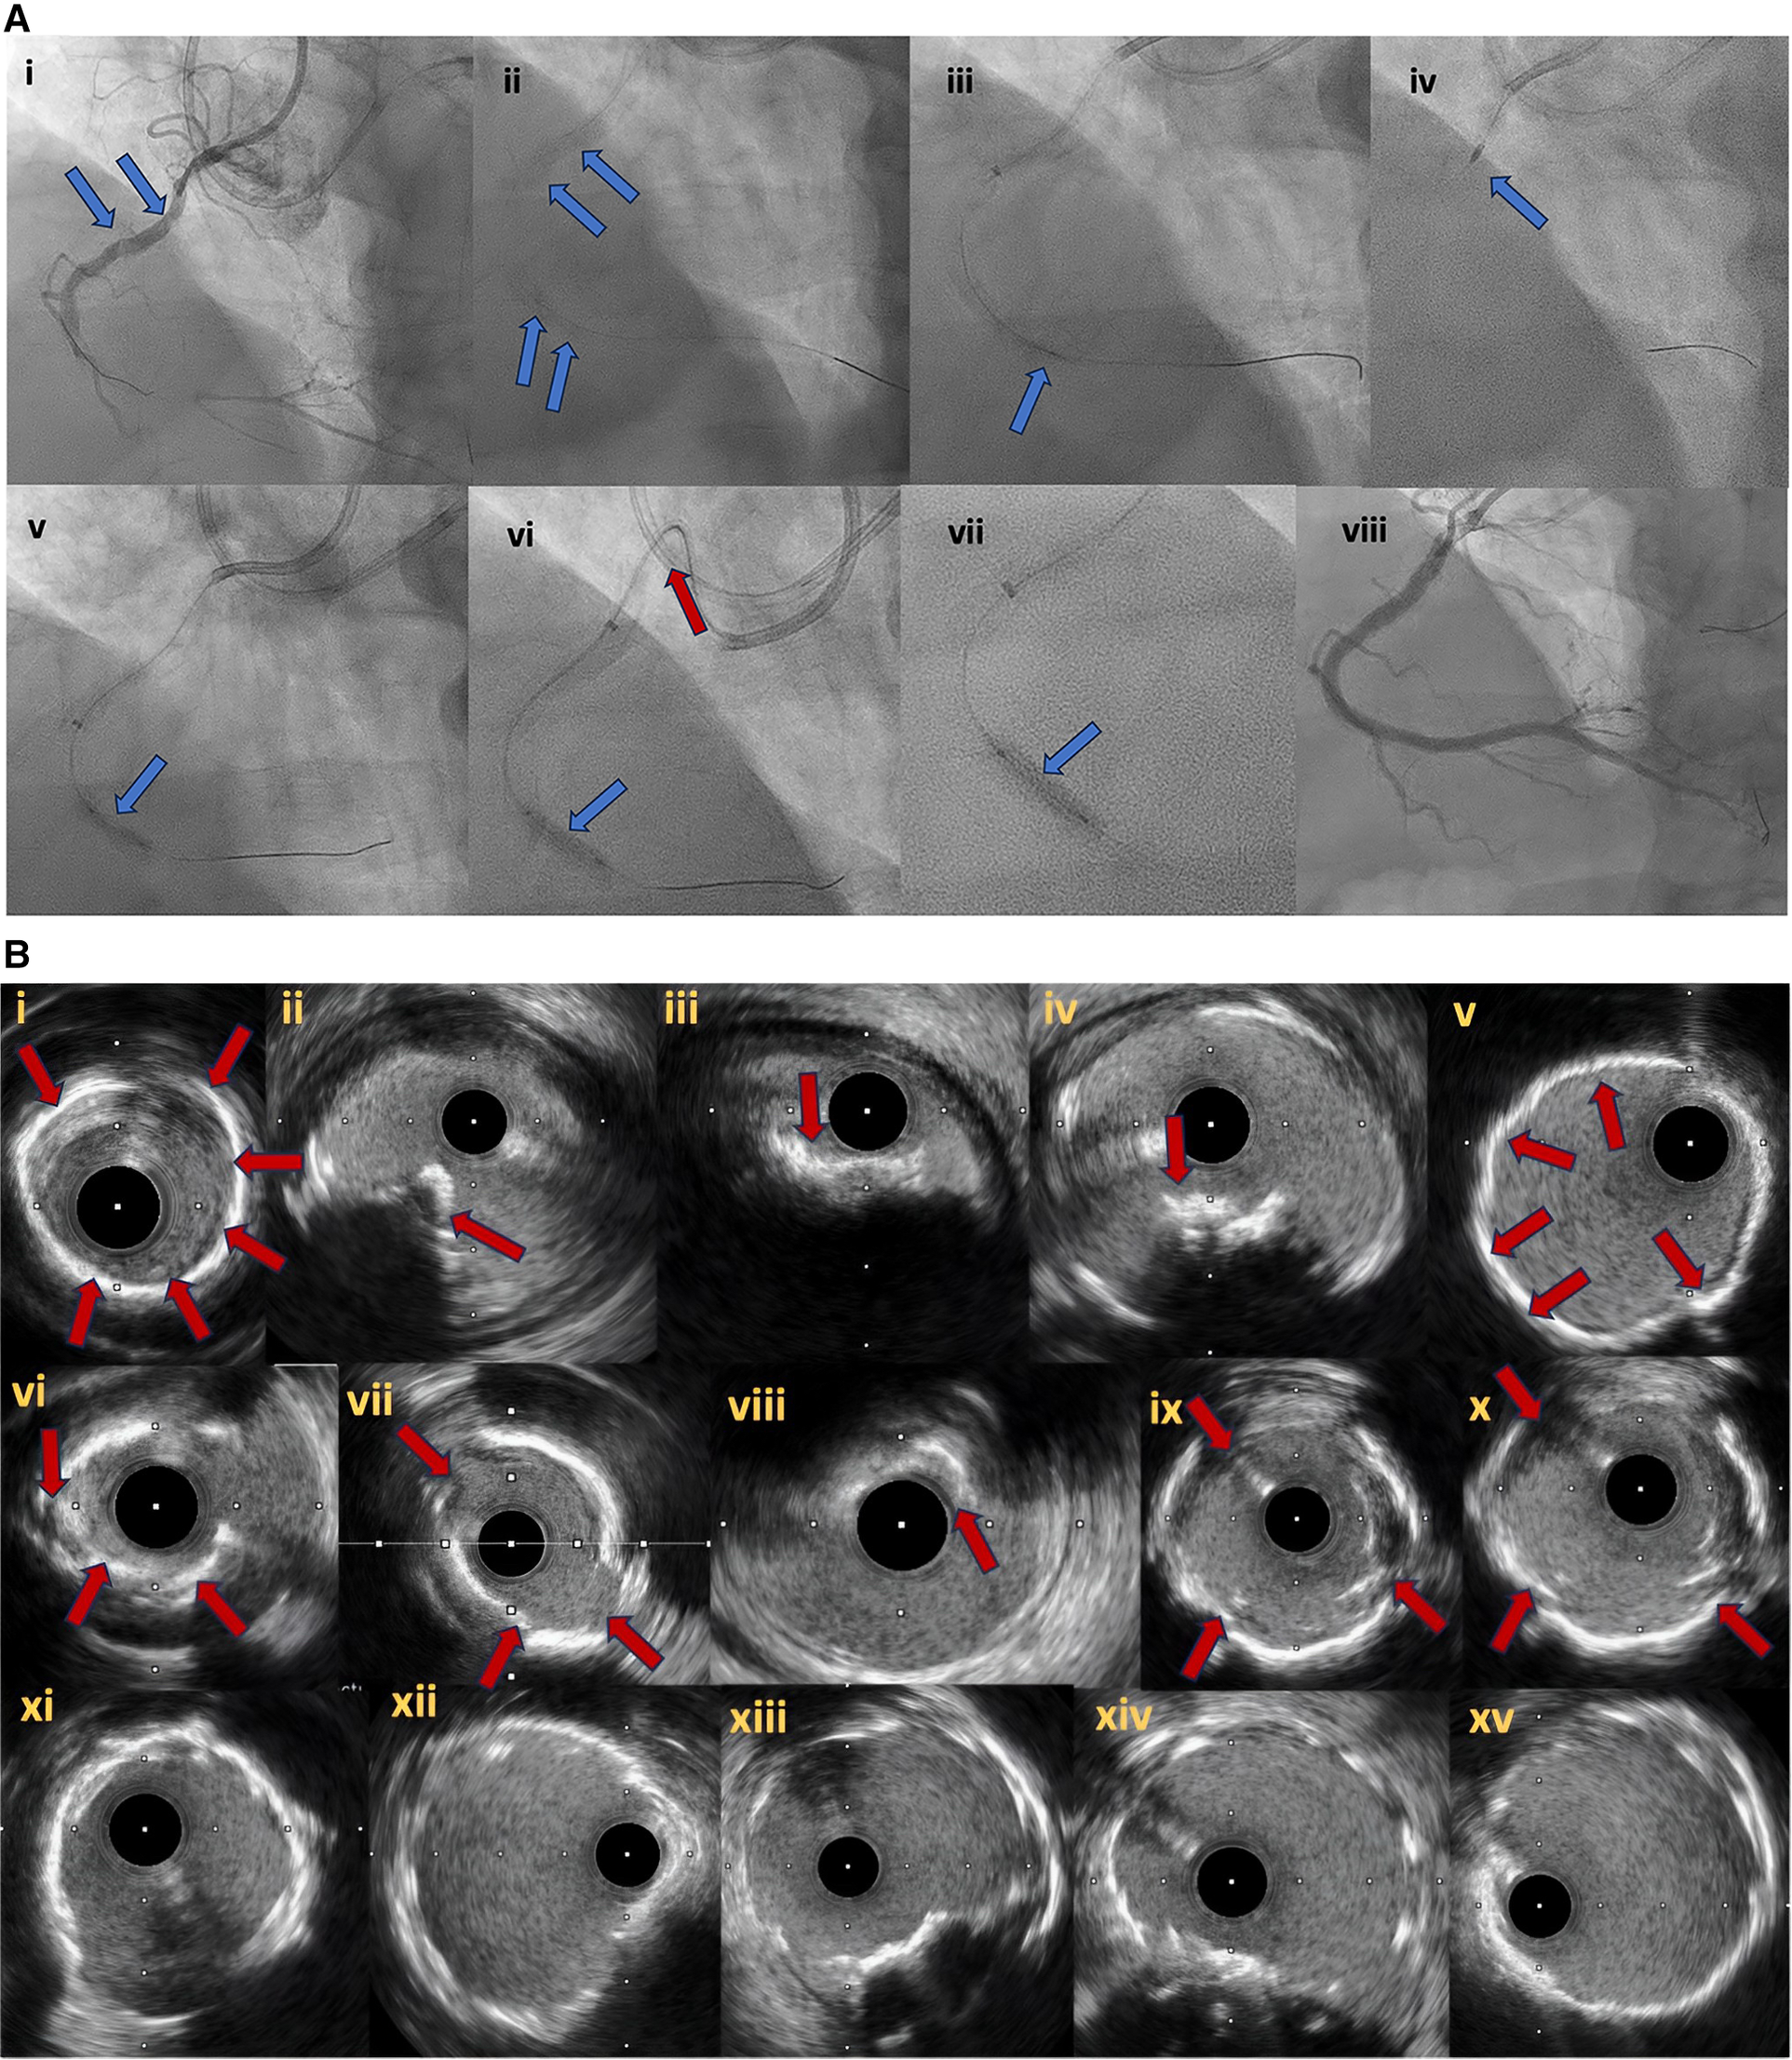

Figure 4

Antegrade and retrograde guidewire positions as assessed by IVUS in reverse CART. (A) Antegrade and retrograde guidewires are both within intimal plaque. This is the ideal scenario to make a connection, after antegrade balloon dilation in the chronic total occlusion body. If needed, retrograde puncture of intimal plaque with a stiffer wire could be performed. (B) Antegrade and retrograde guidewires are both within the subintimal space. This is another ideal condition in which it is easy to create a connection in the same space after balloon dilation. (C) Antegrade guidewire in intimal plaque but retrograde guidewire in subintimal space. This is a very complex situation in which it is crucial to create a medial disruption with proper balloon sizing to create a connection between the two guidewires. In case of failure, it may be possible to advance the antegrade wire distally to enter the subintimal space and create the previous condition (subintimal–subintimal). (D) Antegrade wire in subintimal space but retrograde wire in intimal plaque, often very calcified. This is the most complex situation because antegrade balloon dilation usually enlarges the subintimal space (increasing intramural hematoma) with low probability of creating a connection between the two guidewires. In this situation, the connection is usually achieved by pushing the retrograde wire in the subintimal space (usually with retrograde knuckle technique). In such a complex case, a possible less-used alternative is retrograde balloon dilation (original CART) to create medial dissection and facilitate antegrade guidewire connection with the retrograde guidewire. CART, controlled antegrade retrograde tracking; IVUS, intravascular ultrasound. Modified with permission from Galassi AR, Sumitsuji S, Boukhris M, et al. Utility of intravascular ultrasound in percutaneous revascularization of chronic total occlusions: an overview. JACC Cardiovasc Interv 2016; 9:1979–91, Elsevier. Used with permission from Brilakis ES. Manual of chronic total occlusion interventions a step-by-step approach. Second edition. ed. London: Elsevier/Academic Press; 2018.

Figure 6

(A) Right coronary artery CTO (6Ai). In (6Ai, Aii) angiographic evidence of heavy calcification is noticed (blue arrows). Grenadoplasty is performed (6Aiii, blue arrow) to facilitate microcatheter and balloon crossing followed by rotational atherectomy. Undilatable lesion (6Av, blue arrow) was successfully treated with intravascular lithotripsy (6Avi, Avii, blue arrows). In (6Avi), the tension to the guide extension and catheter during balloon forward motion due to heavy vessel calcification is noticed (red arrow). Final angiographic result after successful CTO recanalization and plaque modification with combined grenadoplasty, rotational atherectomy and intravascular lithotripsy (6Aviii). (B) intravascular ultrasound pictures. Different modes of calcification including circumferential thick calcification (6Bi, 6Bv) and calcified nodules (6Bii–iv, red arrows). The effect of plaque modification techniques (grenadoplasty, rotational atherectomy and intravascular lithotripsy) is demonstrated in (6Bvi–x). Final intravascular images after successful stents insertion (6Bxi–xv).